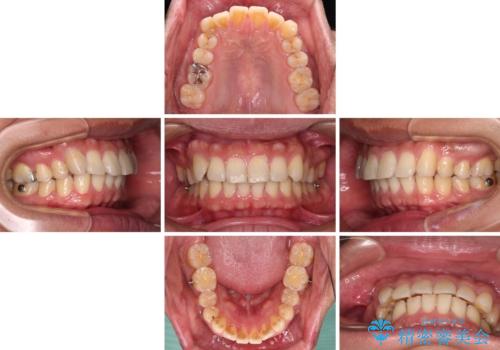

- 20代男性

- インビザライン

- 4年8ヶ月

- 前歯のデコボコを気にして来院された患者様です。

当院でインビザライン矯正治療をされている方からのご紹介ということで、インビザラインでの矯正治療をご希望でした。

ワイヤー矯正に比べ来院頻度は低いものの、新幹線での通院のため、やや治療期間が延びることが懸念されました。

配属異動や長時間勤務などによりインビザラインが十分に装着できない期間があり、インビザライン有効期限5年間ギリギリとなってしまいました。